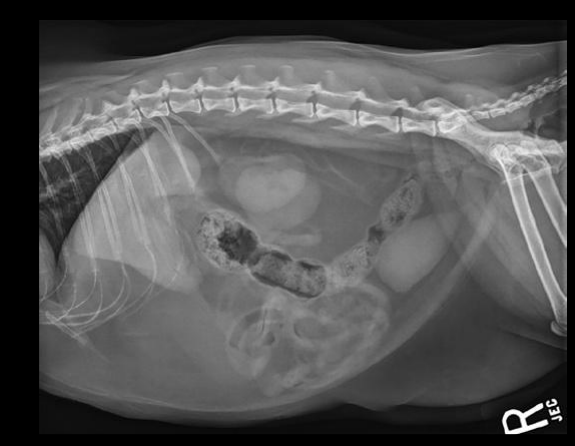

Radiografia laterolateral

Dependiendo de la posición los gases van a un lado o a otro: Decúbito lateral derecho Radiografía Lateral

- Gas en fundus

- Se ve mejor cola del bazo

- Mayor separación de siluetas renales

Decúbito lateral izquierdo

- Gas en píloro

- Mejor visualización delduodeno

Que NO se ve en una radiografia en condiciones normales

- Páncreas

- Glándulas adrenales

- Vesícula biliar

- Uréteres

- Uretra

- Nódulos linfáticos

- Vasos sanguíneos

- Ovarios

- Útero no gestante